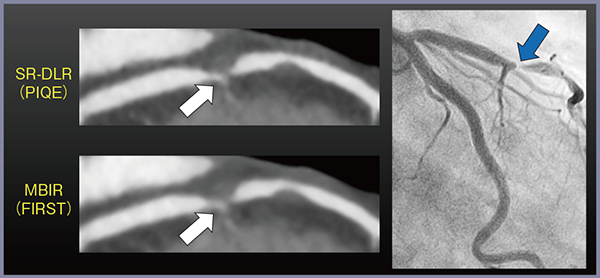

DLRは,高精細CTを用いた冠動脈CTの検査スループットの向上に大きく貢献したが,320列ADCTと比較し高精細CTでは検査対象が洞調律に限られることや,被ばく線量が増大するなどの課題が残されている。そこで登場したのが超解像DLR“Precise IQ Engine(PIQE)”である。PIQEは,高精細CTのデータにFIRSTやAiCEで培ったモデルベースの高分解能かつ低ノイズな画像をDCNNの学習に使用することで,320列ADCTの画像を高分解能化する技術である。実際に,左前下行枝の高度狭窄病変について,320列ADCTで撮影しFIRSTおよびPIQEで再構成した画像を冠動脈造影画像と比較したところ,内腔の視認性や短軸像におけるプラーク辺縁の描出はFIRSTよりもPIQEの方が優れていた(図5)。

図5 320列ADCTによるFIRST,PIQE,冠動脈造影の比較